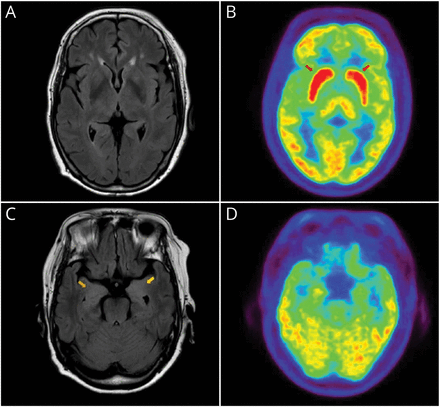

我们与轴向削减显示基底神经节(A和B)和内侧颞叶(C和D) fluid-attenuated反转恢复(天赋)的MRI和18F-FDG-PET。摄影图像显示突出的葡萄糖代谢亢进在双边基底神经节(B,红色箭头)。天赋的图像显示微妙hyperintensities在内侧颞叶(C,黄色箭头)。

大多数anti-LGI1脑炎病例表现为认知功能障碍、精神症状,或癫痫发作。自主功能障碍很少触发器及时anti-LGI1脑炎的诊断。1我们进行了anti-LGI1抗体测试,由于特征正发现。这种情况下说明基底神经节和内侧颞叶代谢亢进anti-LGI1脑炎是两个不同的目标,虽然可以找到类似的发现在其他类型的自身免疫性脑炎(例如,anti-NMDA anti-IgLON5)或自身免疫性舞蹈病。2,3